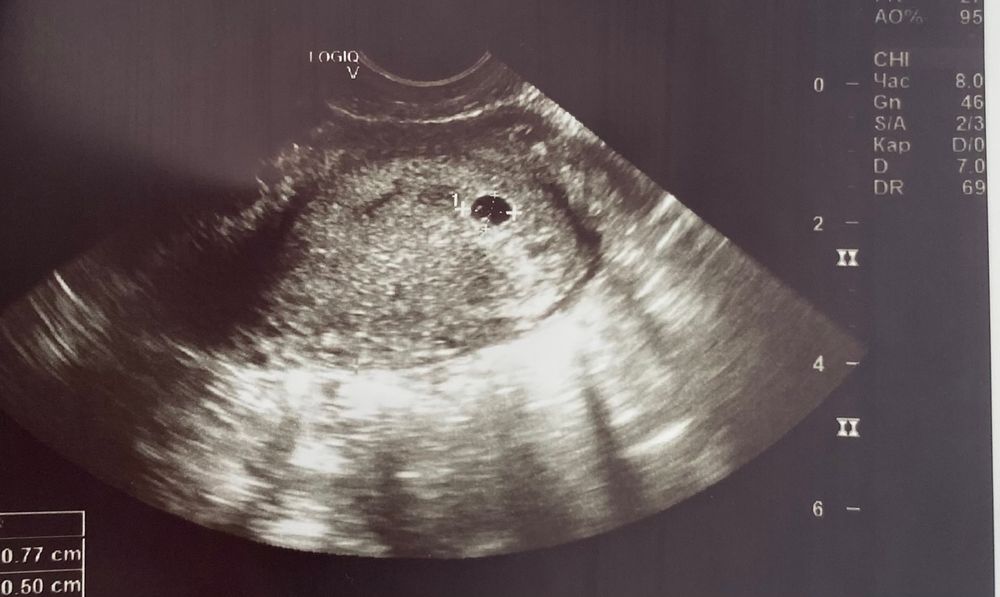

Узи герцена 1 курск 67 фото